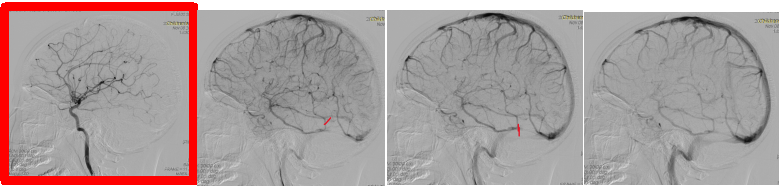

到了8月底,经过一系列治疗,虽然眼压正常,但双眼仍有乳头水肿。在2020年9月初进行了包括VEP和OCT在内的一系列眼科检查,同期未见明显的临床好转。9月11日至17日又对妮妮进行了头部核磁共振检查,发现双侧视神经走行迂曲,双侧乙状窦变薄。同时影像学表现脑室小。

目前可以考虑的可能原因是MRI血管图像显示的乙状窦狭窄

这些狭窄会阻碍静脉血从颅骨排出,从而增加颅内液体的含量和压力

然而,我们确实看到后颅窝窦狭窄与丰富静脉增生有关。对于这种现象,我们只能等待,希望得到一个可能需要很长时间的自行缓解。但在这期间仍需要降低颅内压。

另外,也可以考虑乙状窦狭窄的支架置入术。